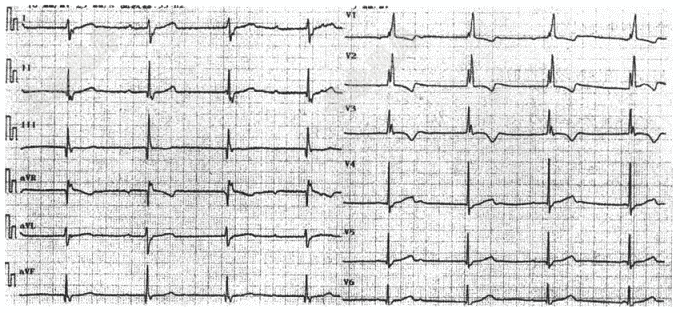

- 单项选择题请选出正确诊断( )

A、窦性心律、完全性右束支传导阻滞

B、窦性心动过缓

C、窦性心律、不完全右束支传导阻滞

D、交界性逸博、完全右束支传到阻滞

E、窦性心动过缓、完全右束支传到阻滞